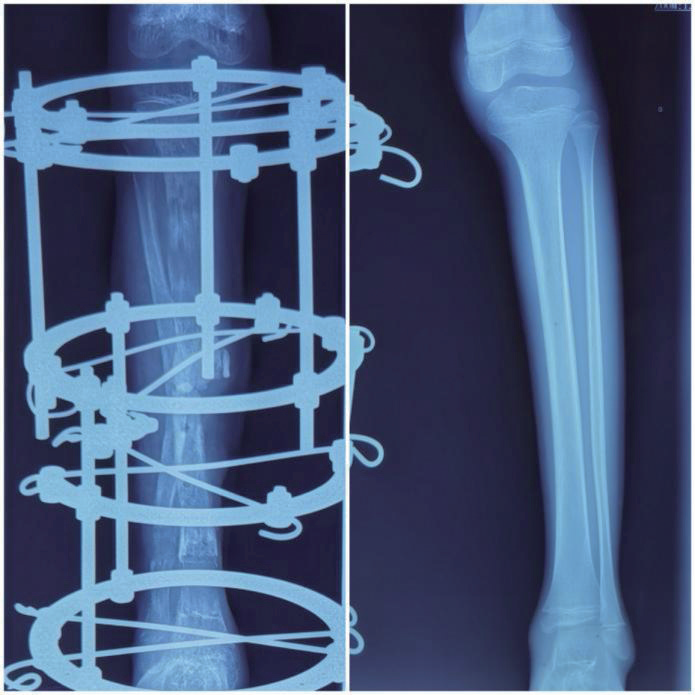

术前评估显示,患儿右小腿明显短缩,皮肤可见多处陈旧手术瘢痕,踝关节呈30°固定内翻,足部力线严重异常,无法负重(图5)。X线片提示右胫骨中段骨不连、断端硬化萎缩、内固定松动,腓骨代偿性增粗弯曲,踝关节面倾斜,符合创伤后骨缺损合并继发性踝关节畸形的典型表现,最终诊断为右胫骨创伤后大段骨缺损伴踝关节固定性内翻畸形(图6)。

image.png

图6 术前X线片

术后管理是确保手术成效的关键环节。手术团队在术后第7天启动骨搬运程序,以每日1 mm的速度分4次调节螺纹杆,推动近、远端骨块向缺损中心同步靠拢(图7)。每周通过X线监测骨再生进展及对合端对位情况,待原3.5 cm骨缺损闭合后,继续延长4.0 cm,直至双下肢恢复等长。针道护理严格执行每日酒精消毒,有效预防感染。康复方面,术后第2天即指导患儿进行股四头肌等长收缩及膝、踝关节主动活动,并鼓励拄拐部分负重行走,以促进局部血运与骨再生。整个过程密切防范轴偏、关节挛缩等并发症,及时调整外固定支架,保障搬运过程顺利。术后6个月影像学评估显示,骨缺损已完全修复,再生骨矿化良好,踝关节力线恢复正常,双下肢长度一致。功能上,患儿可实现独立行走,步态基本对称,踝关节稳定且无疼痛,实现了结构与功能的双重康复。

图7 骨搬运治疗后X线片